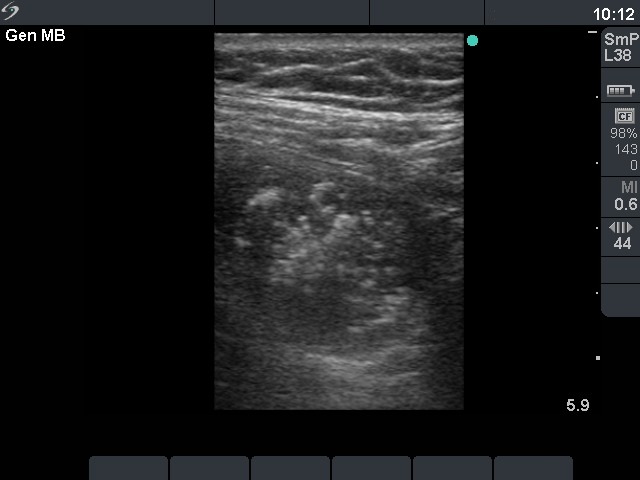

First examination (first row of images)

Clinical data: a 56-year-old man was referred for an evaluation of a recurrent nodular goiter. He was operated 14 years ago, histopathology resulted in benign, hyperplastic nodules. He had no complaints.

Palpation: a multinodular goiter.

Functional state: euthyroidism (TSH 0.69 mIU/L, FT4 12.4 pM/L).

Ultrasonography: both thyroids were enlarged and echonormal. There were multiple, moderately hypoechogenic nodules in both lobes. There was a hypoechogenic nodule in the central part of the left lobe which presented hyperechogenic patches containing bright, hyperechogenic punctate granules. This pattern is similar to that observed in medullary cancer. The vascularization was not specific.

FNAC: was repeatedly not diagnostic.